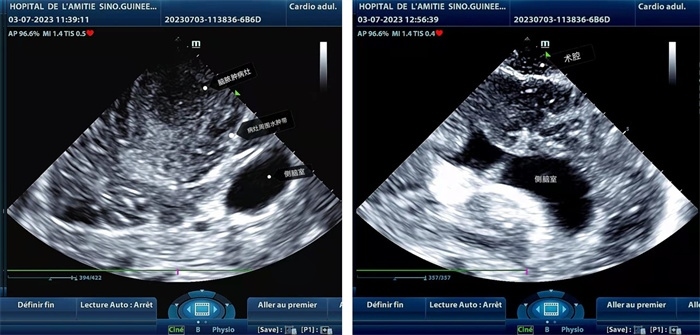

手術(shù)中,張國濱在超聲科顧秀娟的幫助下,運(yùn)用顱腦術(shù)中超聲技術(shù),通過將一次性保護(hù)套的超聲探頭置于腦組織表面,實(shí)時(shí)觀察病變的位置和形態(tài),進(jìn)一步確認(rèn)最佳手術(shù)路徑。術(shù)中超聲顯示,病變位于左額頂葉,大小約為4x4x3cm,邊界清晰,呈囊實(shí)性,周邊腦組織水腫明顯。最終,病灶順利切除,診斷為腦膿腫,并通過超聲檢測(cè)確認(rèn)術(shù)腔無病變殘留、無出血,為患者術(shù)后恢復(fù)提供了良好的保障。

左圖顯示術(shù)中超聲見囊實(shí)性病變,大小約為4x4x3cm,病灶周圍腦組織水腫明顯;右圖為病灶切除后,術(shù)中超聲示術(shù)腔無病變殘留

左圖顯示術(shù)中超聲見囊實(shí)性病變,大小約為4x4x3cm,病灶周圍腦組織水腫明顯;右圖為病灶切除后,術(shù)中超聲示術(shù)腔無病變殘留。中國第二十九批援幾內(nèi)亞醫(yī)療隊(duì)供圖